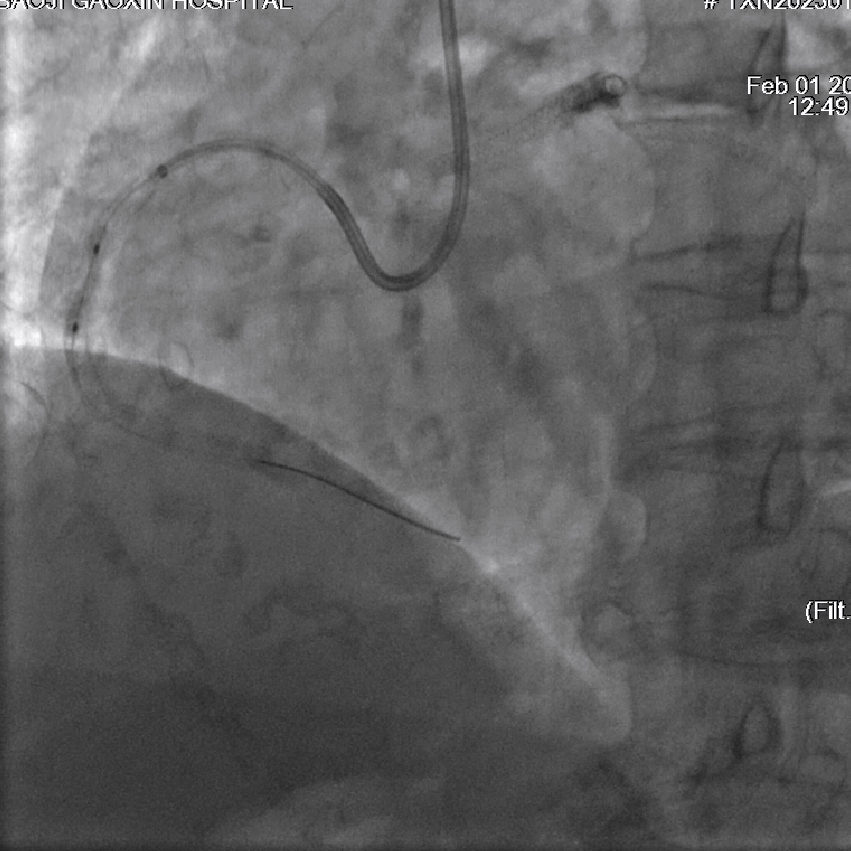

图3 IVUS示右冠中段支架膨胀不良,支架内多处可见新生钙化病变

该患者入院后,完善相关检查并再次建议行CABG治疗,但家属仍拒绝,遂考虑再次行PCI手术干预。冠脉造影提示患者冠脉右冠状动脉中段70-95%再狭窄,左主干末端80%狭窄,前降支原支架中远段 80-95%再狭窄,回旋支完全闭塞,急需手术尽快解决冠脉血流灌注问题,否则随时有生命风险,但患者多处支架内/节段内再狭窄,造影提示钙化明显,外院已尝试无法扩张,经手术团队充分讨论后,计划在IABP支持下,先进行右冠状动脉干预,利用IVUS精准评估原支架再狭窄部位情况,采用旋磨或Shockwave冲击波球囊处理无法扩张的病变部位,右冠处理后择期进行左冠状动脉干预。在制定了详尽的手术计划后,手术团队首先对患者的右冠状动脉行IVUS检查,结果提示该患者右冠中段支架局部膨胀不良,局部支架面积6.67mm²,管腔内多处可见钙化小结及270°以上钙化,IVUS钙化积分达3分。由于膨胀不良处原支架后方可见钙化斑块,常规旋磨效果不佳,对于此类钙化病变,IVL处理是最佳方案。手术团队对近端采取棘突球囊及高压球囊进行扩张,采用Guidezilla辅助下输送3.0mmx12mm Shockwave冲击波球囊于右冠钙化处进行冲击波钙化斑块碎裂术,通过IVUS证实支架内的新生钙化病变得到松解,原膨胀不良部位支架面积达到7.76mm²,后经过高压球囊充分预处理,顺利完成右冠支架植入,术后复查右冠原膨胀不良部位支架面积9.17mm²。